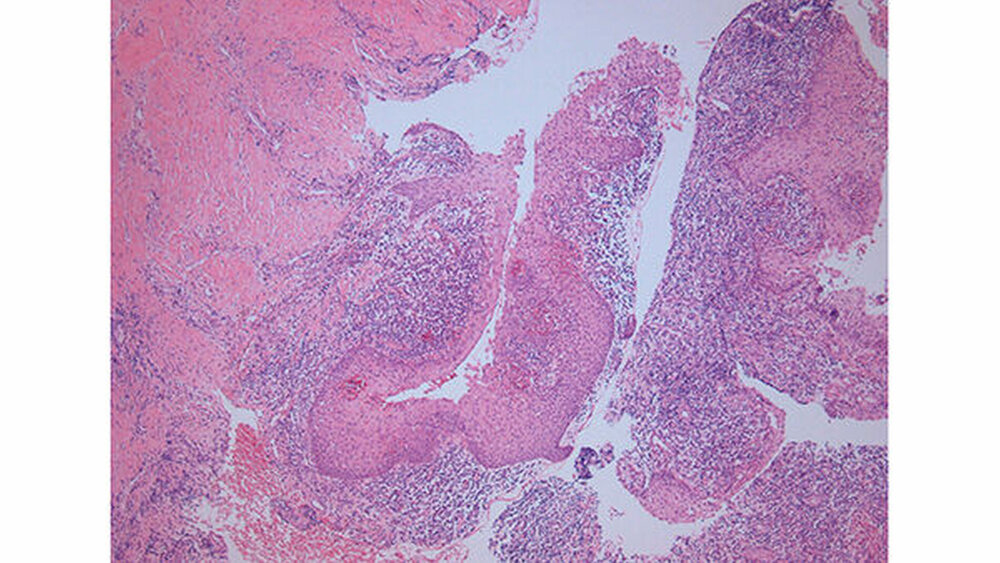

Der histopathologische Befund zeigte eine nasopalatinale Zyste mit mehrschichtig unverhornter plattenepithelialer Auskleidung und bandförmiger chronischer, fokal florider unspezifischer Entzündung (Abbildung 7).

Differenzialdiagnostisch kommen bei Kieferzysten Pseudozysten, keratozystisch odontogene Tumoren (KCOT), Ameloblastome, Knochensystemerkrankungen sowie benigne Kiefertumoren (zentrale Fibrome und eosinophile Granulome) als auch maligne Kiefertumoren (zentrales Kieferkarzinom, Zystenkarzinome oder ossäre Metastasen) in Betracht. In der Histologie zeigt sich bei dieser Zystenentität bei einer verstärkten Entwicklung zur Mundhöhle hin vermehrt Plattenepithel, bei einer weiter nasal orientierten Lage Flimmerepithel des Respirationstrakts, wobei auch Kombinationen aus beiden Epithelien in der Literatur beschrieben werden [Anneroth et al., 1986].